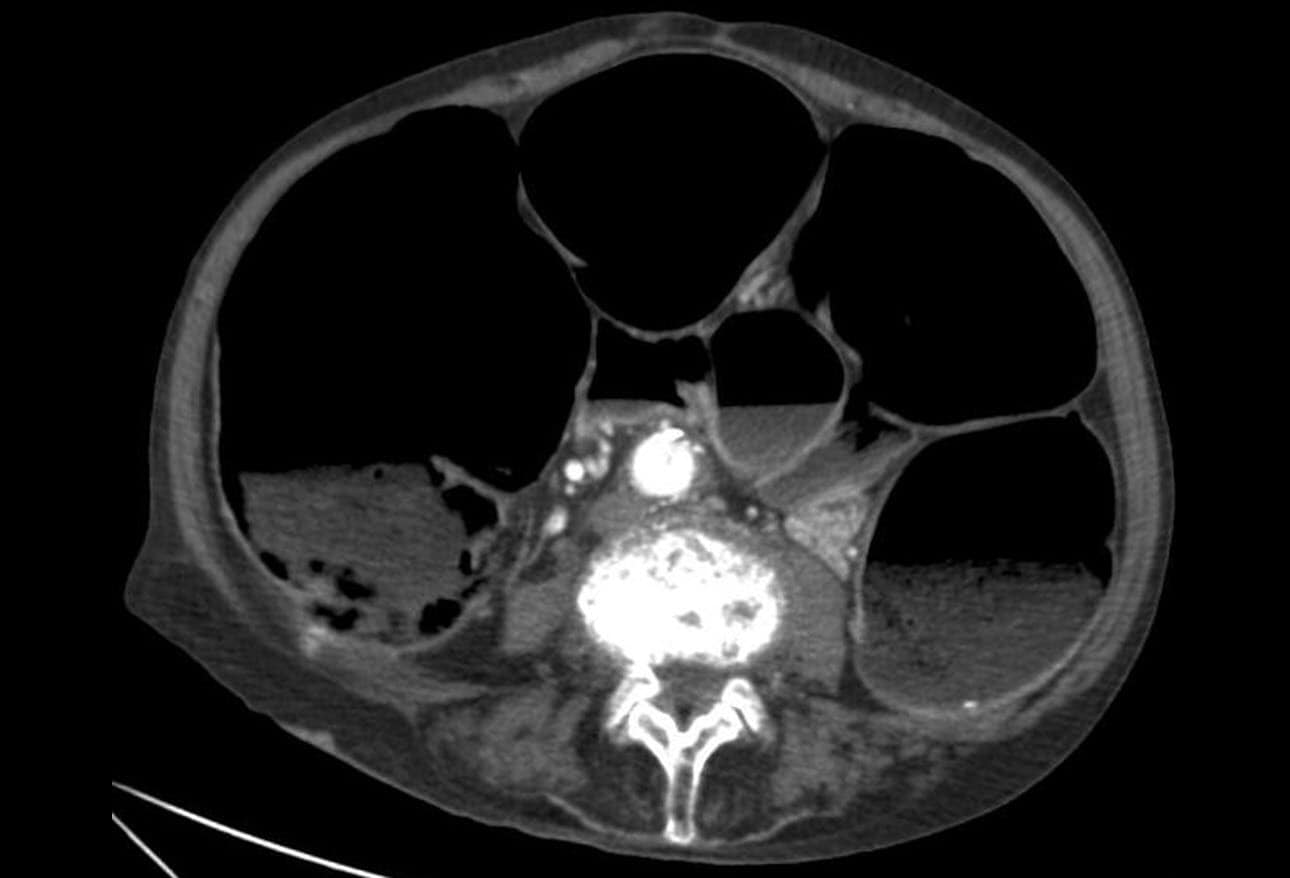

From radiopaedia.org

Ogilvie syndrome Image Ogilvie Collision we're fully equipped with all the automotive body repair tools, equipment, and skilled labor to deliver the best service to you. oglivie collision auto body & restoration is open mon, tue, wed, thu, fri. ogilvie collision is a reputable auto body repair shop in ogilvie, mn, specializing in collision repair services. Body shops, auto glass services. Ogilvie Collision.